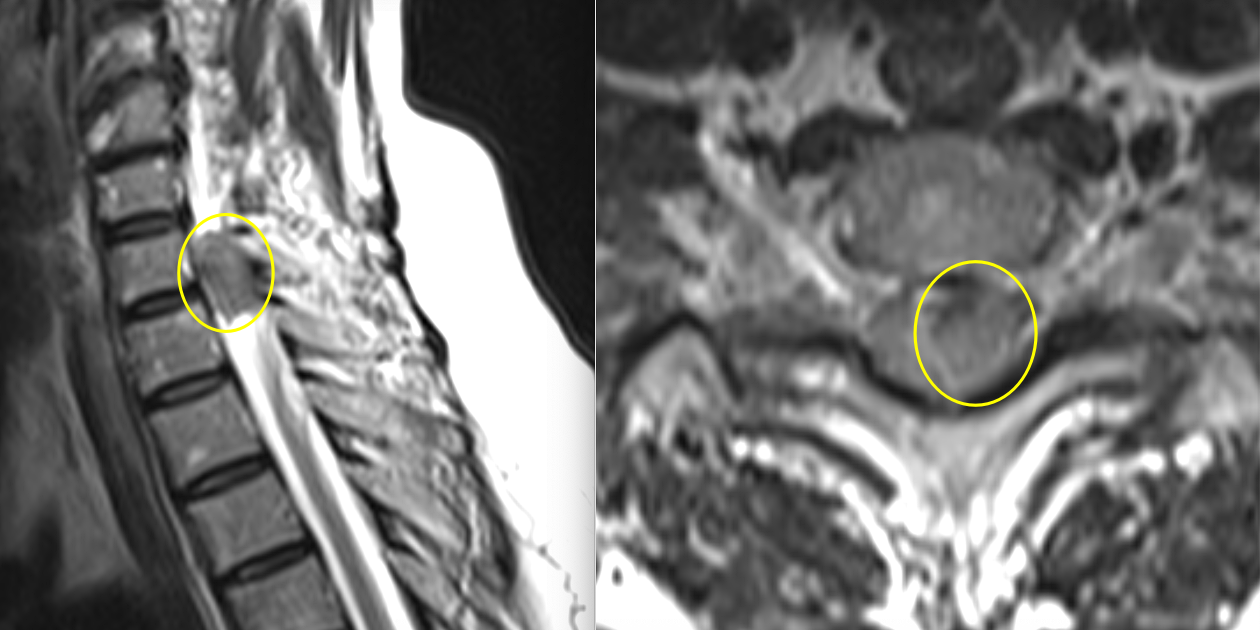

Investigația RMN spinal a evidențiat o formațiune intradurală extramedulară situată la nivel C7–T1, pe partea stângă.

Tumora prezenta caracteristici imagistice sugestive pentru un meningiom: leziune bine delimitată, cu captare omogenă de contrast, cu inserție pe meninge și efect de masă asupra măduvei.

Deși dimensiunea nu era foarte mare, localizarea era critică. La acest nivel, fibrele nervoase care controlează mișcările membrului superior sunt organizate compact, iar orice compresiune — chiar moderată — poate duce la deficit motor progresiv.

Măduva apărea deviată și comprimată, cu dispariția spațiului lichidian din jur — semn clar că structurile nervoase nu mai aveau spațiul necesar funcționării normale.